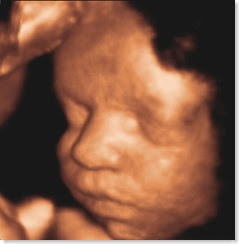

3d 4d Ultrasound Peoria Il

Mommy Vision 3d 4d Ultrasound Home Facebook